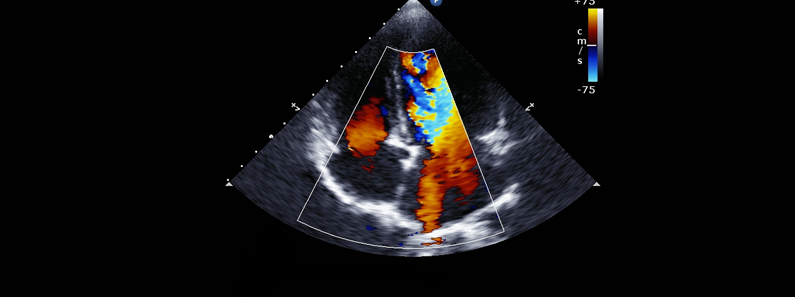

Color Doppler

Color Doppler imaging is a non-invasive ultrasound technique used to visualize blood flow within the body's arteries and veins. At Namratha Hospital, we utilize advanced Color Doppler technology to assess blood circulation, detect abnormalities, and aid in the diagnosis of various medical conditions.

• Visualizes blood flow in arteries and veins

• Assesses blood flow speed, direction, and characteristics

• Detects vascular disorders and heart conditions